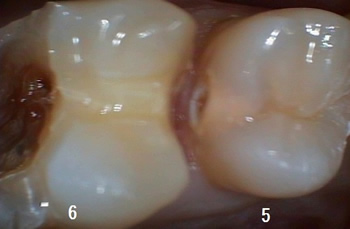

そっと茶色の虫歯を削っていきましたが、黒い点が2つ(歯髄)出てきました!

おそらく虫歯が深く感染しており、半分は失活(死んでる)しているようです!

この裏側にも穴があり、これから削るのですが、、、、 |

|

ここを削ると、手前の5番目の歯がまる裸になりますので写真をパチリ!

これをお見せすると「本当に穴があいていたんですね~!」と納得されます!

案外と大きいので応急処置で次回とりかかります、、、

という風に、、、 |